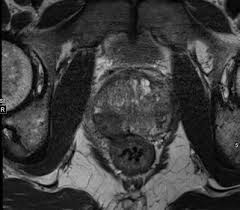

МРТ малого таза (полное название магнитно-резонансная томография) — это детальное, неинвазивное сканирование мочеполовой системы женщины и мужчины. По своей безопасности и безвредности она сопоставима с ультразвуковым сканированием, однако информационная точность и ценность данного обследования в разы выше.

Как делают МРТ органов малого таза у мужчин

Томография области малого таза у мужчин может проходить двумя способами:

- внеполосное — это когда МРТ катушка ставится сверху на область исследования, и пациент завозится внутрь томографа. Метод неинвазивный и не причиняет никаких неприятных ощущений.

- внутреннее – здесь используется специальная эндоректальная катушка, которая вводится в прямую кишку. Этот метод обладает наибольшей разрешающей способностью, но у чувствительных мужчин может вызвать легкий дискомфорт. В ходе ректального МРТ органов малого таза снижается расстояние между МРТ катушкой и приемником, что всегда улучшает качество получаемых снимков.